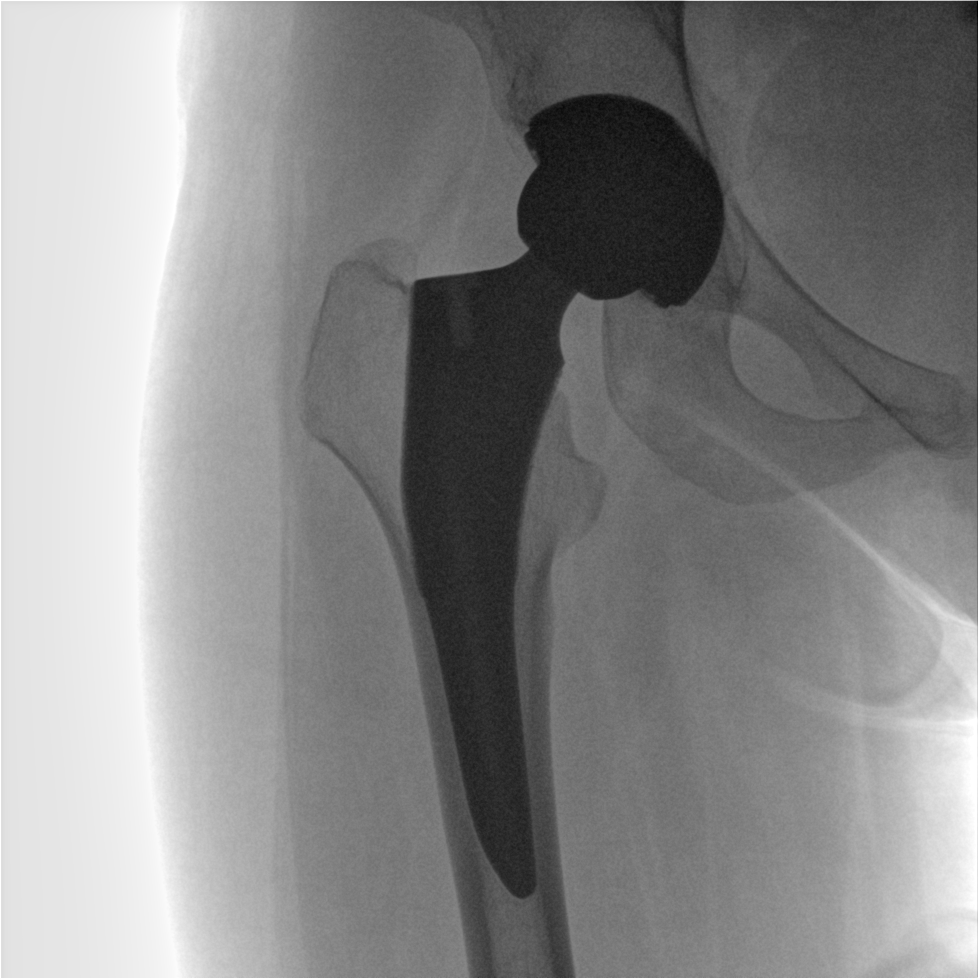

成像清晰、操作簡易、擺位便捷,主要適用于骨科、脊柱外科、矯形外科、創(chuàng)傷骨科及手術(shù)室等,能大幅度提升手術(shù)水準(zhǔn),降低手術(shù)風(fēng)險(xiǎn)和并發(fā)癥的概率。

提供更大的術(shù)中三維成像視野,采集更多圖像信息,可一次拍全全段頸椎、全段腰椎、七節(jié)胸椎、雙側(cè)骶髂關(guān)節(jié)、股骨頭及單側(cè)盆骨。